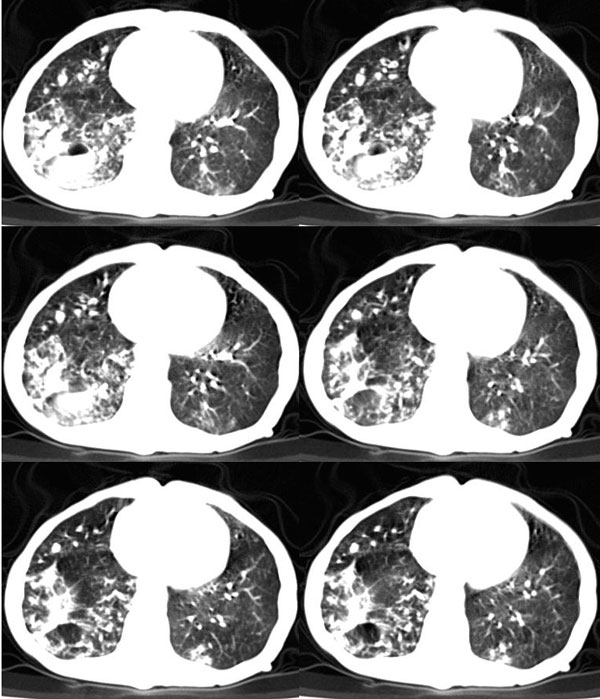

女:73岁;因一月前感冒后咳嗽,发烧,有大量脓痰,并且有恶臭味。

5毫米局部薄平扫

局部5毫米强化

肺窗

右肺下叶示片状致密影密度不均,内见一空洞有宽液平,并可见壁结节周围示散在斑片模糊影,左下肺亦见一斑片模糊影,考虑 肺脓疡,肺癌不除外。

右下肺脓肿,两下叶,中叶支扩并感染,右侧胸膜肥厚粘连。

发烧,有大量脓痰,并且有恶臭味,空洞,大液平,比较典型的肺脓疡

该患者是我上个月作的,经正规抗炎治疗半月后平片显示吸收。{患者不愿ct复查}